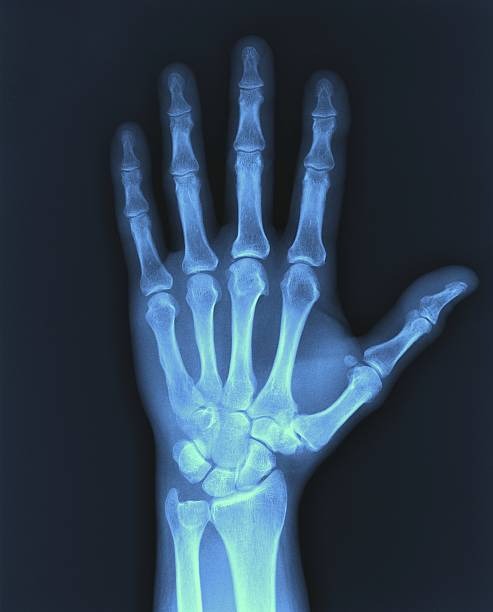

해부학적 이상은 척골충돌증후군의 주요 원인 중 하나로, 팔꿈치와 손목 사이의 뼈 구조나 관절 배열에 선천적 혹은 후천적 변형이 있을 때 발생할 수 있습니다. 예를 들어, 척골이 정상보다 길거나 뼈의 돌출부가 비정상적으로 발달하면 손목과 척골 사이의 공간이 좁아져 충돌이 발생하기 쉽습니다. 이런 구조적 이상은 일상적인 움직임에서도 반복적으로 뼈와 인대, 힘줄 사이에 마찰을 일으켜 염증과 통증을 유발합니다. 해부학적 이상은 개인마다 다르게 나타나며, 증상이 심하면 기능 저하와 만성 통증으로 이어질 수 있습니다. 정확한 진단을 위해 X-ray, MRI 등의 영상 검사가 필요하며, 치료는 보존적 방법부터 수술적 교정까지 다양하게 적용됩니다. 조기에 이상을 발견하고 적절한 관리와 운동으로 관절의 움직임을 개선하는 것이 중요합니다.